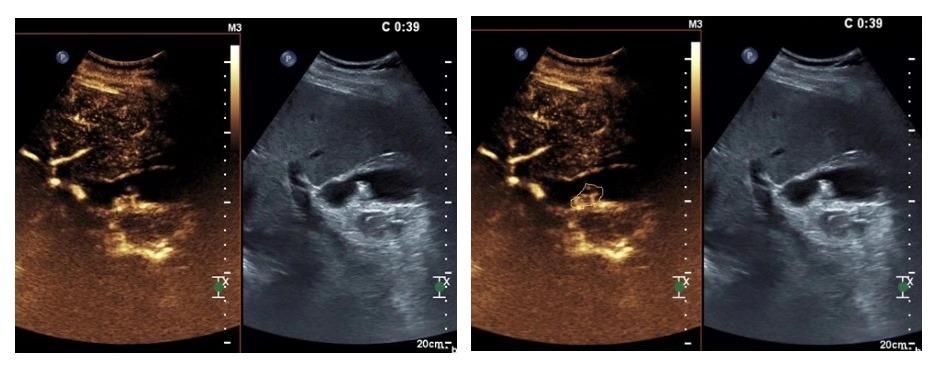

术中即刻造影:可见占位部分强化,仍具有活性,未消融完全。

进行“修补”巩固,再次启动消融,使占位彻底“灭活”。

再次造影可见占位呈动脉期“无强化”,消融完成。